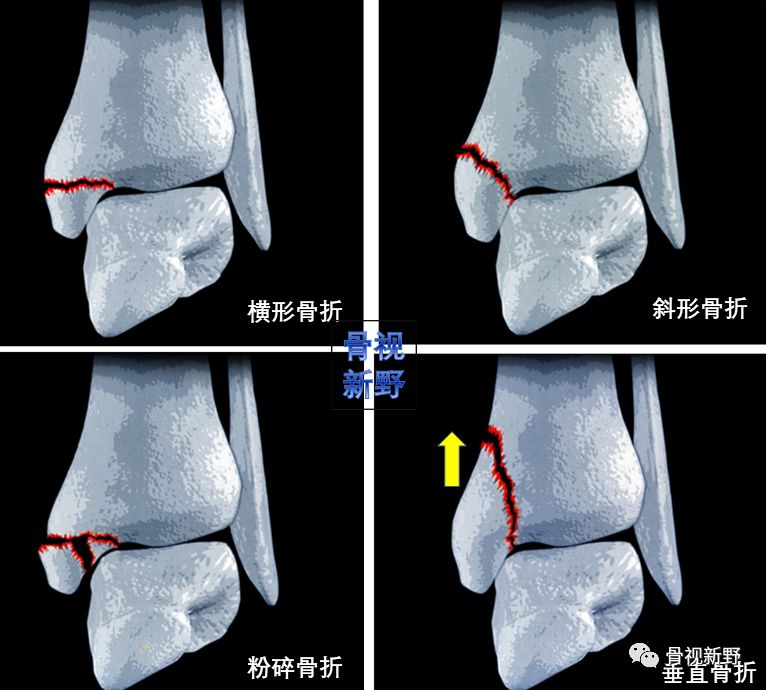

内踝垂直型骨折的buttress固定

内踝骨折根据骨折线走形方向可分为:横形、斜形、粉碎、垂直骨折,其中斜形、垂直形,特别是垂直型骨折的剪力较大,常规克氏针、空心钉、张力带等固定措施不能很好中和剪切力,应用buttress钢板的防滑原理可减少不愈合及畸形愈的并发症。